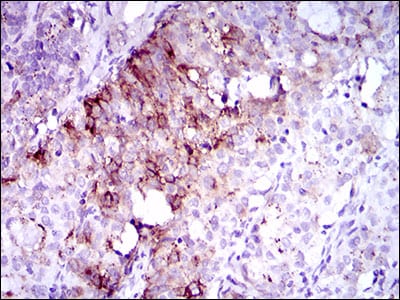

分类: 科研抗体货号: 30507别名: FLK2; STK1; CD135; FLK-2应用: IHC反应种属: Human